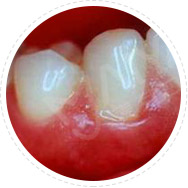

• 牙菌斑、浅龋

麦芽EMS洁牙

麦芽EMS洁牙将超声波洁牙、喷砂洗牙双重洗牙技术二合一,30分钟给你舒适的体验,清洁口内牙菌斑及其附着的牙结石。

适应症:牙面菌斑、牙结石、

牙周袋病菌毒素清除